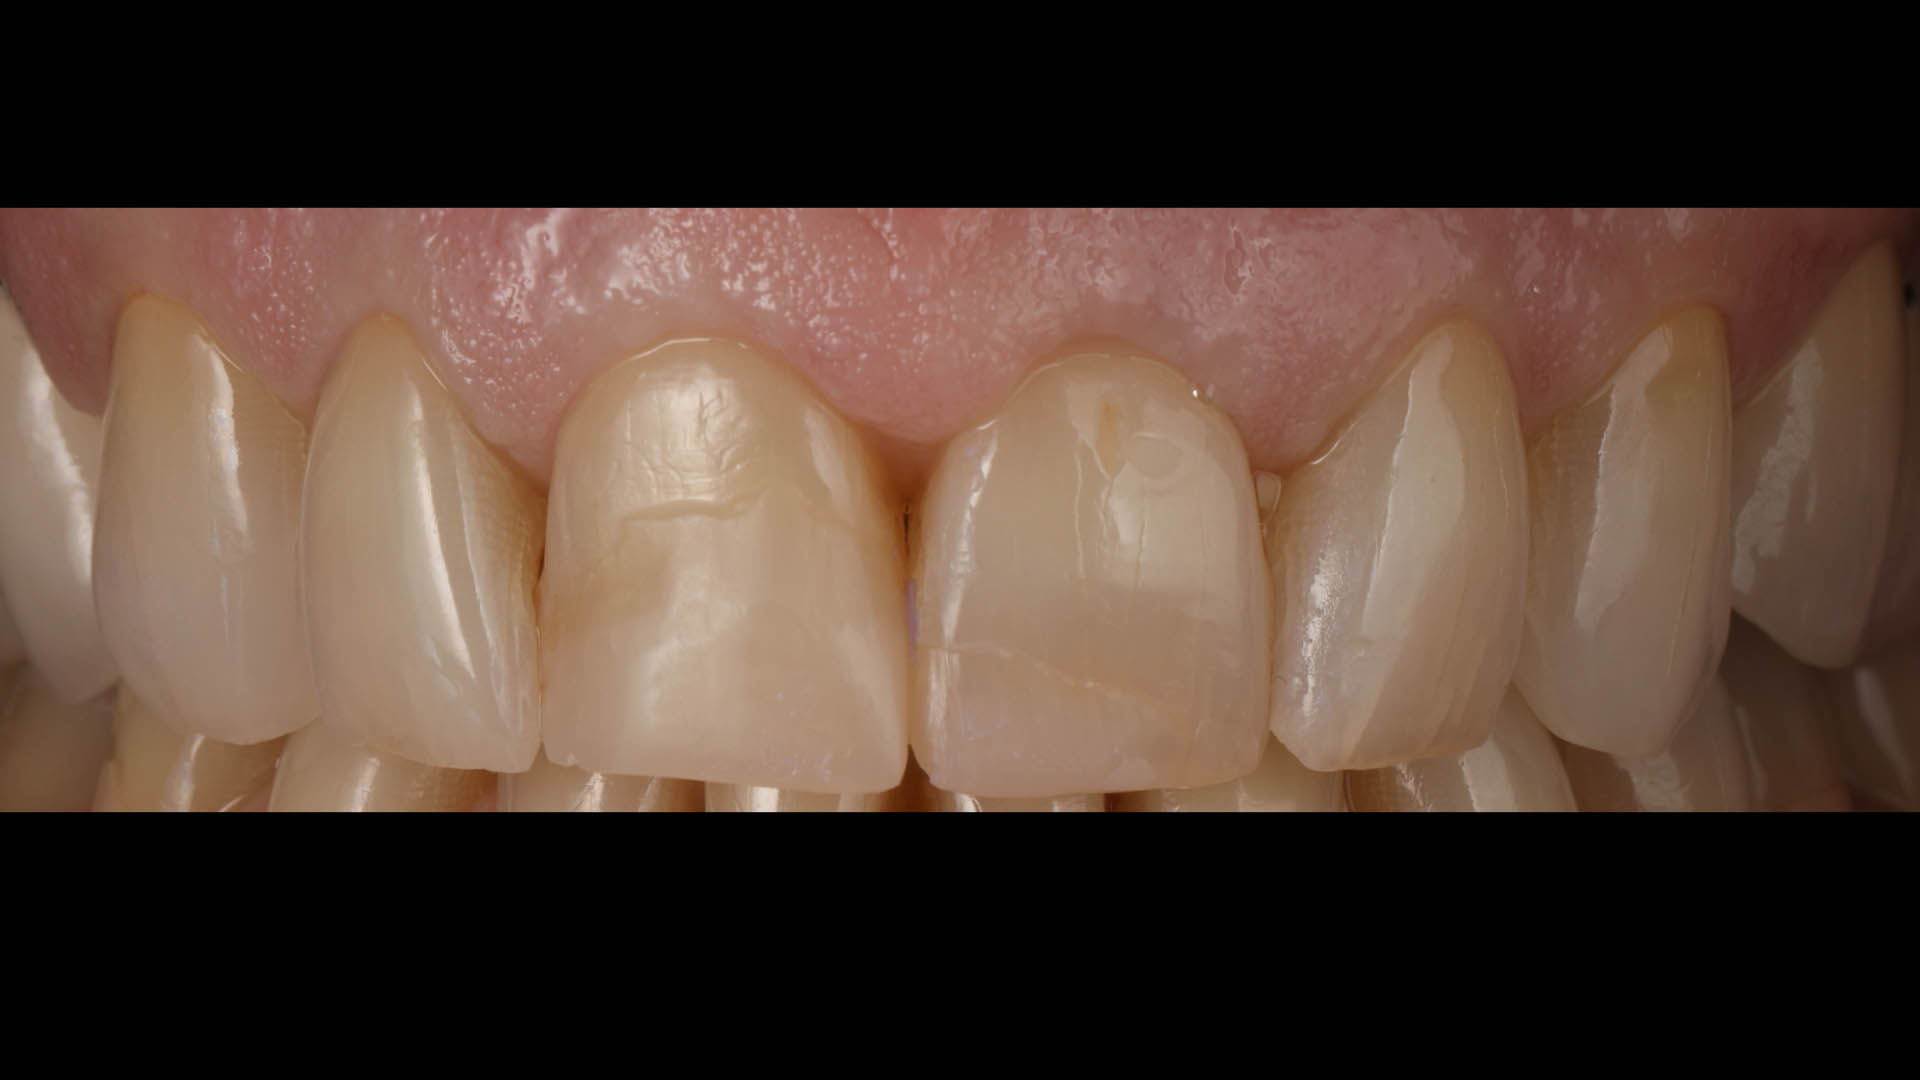

Take a glimpse into the magic of Coral Gables Dentistry through our before and after pictures. See firsthand the incredible smile makeover transformations that have brought confidence and joy to our patients.